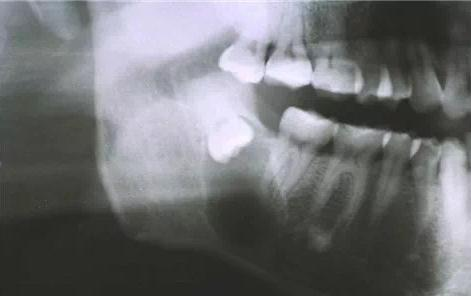

最有效的解决方式首选拔除智齿,但一般由于智齿位置较深,生长方向往往不正常,并且智齿牙根的变异情况比较复杂,所以智齿的拔牙难度和拔牙创伤都会比较大。所以拔除智齿最好采用微创拔牙,以减少拔牙创伤,加快拔牙效率。